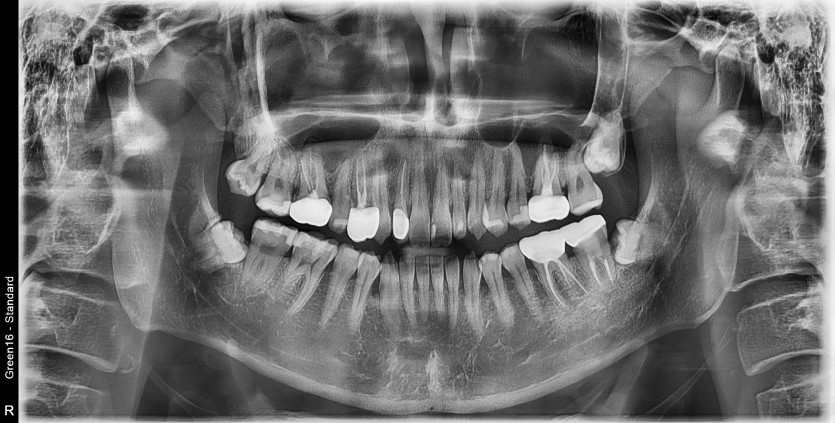

#38,48 사랑니 발치

구강 외과 전문의가 당일발치했습니다.